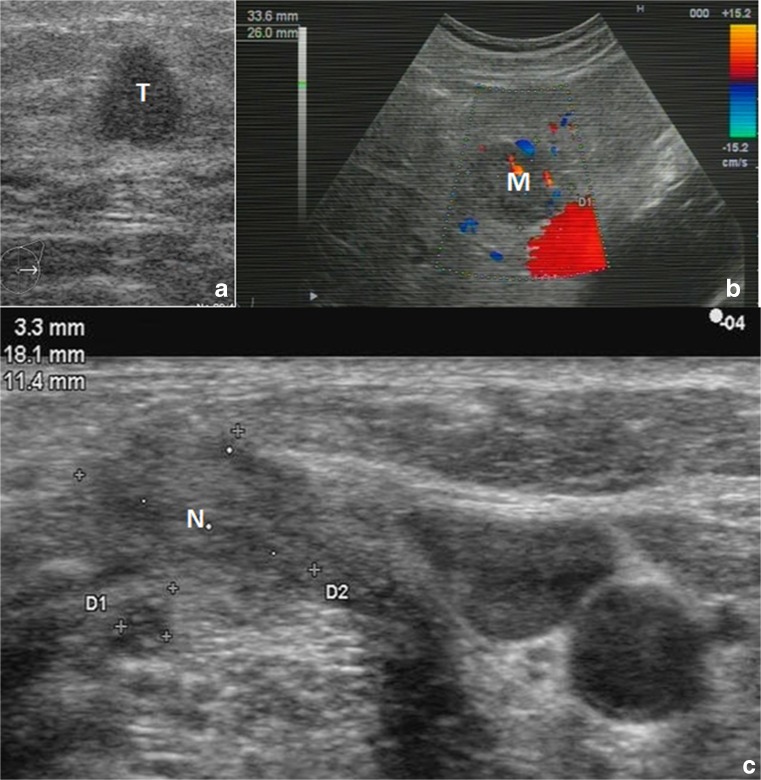

This patient is marked in yellow colour within Table 2. Corresponding medical imaging by ultrasound examination is demonstrated in Fig. 3. A female breast cancer patient, premenopausal, aged 48 years, T1N1M1, with a small tumour (below 1 cm of size) initially detected in the breast followed by multiple-site secondary metastases detected in the bone and liver, has been interviewed for FS symptoms. The interview resulted in 13 positive responses from the maximum of 15 (see “Materials and methods” section). A negative response was given regarding symptom 5 (answered as “rather normal sleep onset”); further, the patient replied as “I do not know” regarding symptom 9 (drug sensitivity). Particularly noticeable responses have been given towards the following symptoms:

Fig. 3.

Medical imaging by ultrasound illustrating the “Case 1” (within the “Metastatic BC—selected cases” section) of the patient diagnosed with the metastatic breast cancer T1N1M1; for the exact description of this case and its relevance for the “Flammer Syndrome”, please see “Results” section. a Small initial tumour in the breast (T). b A metastatic lesion in the liver (M). c A metastasis in the axillary lymph node (N)